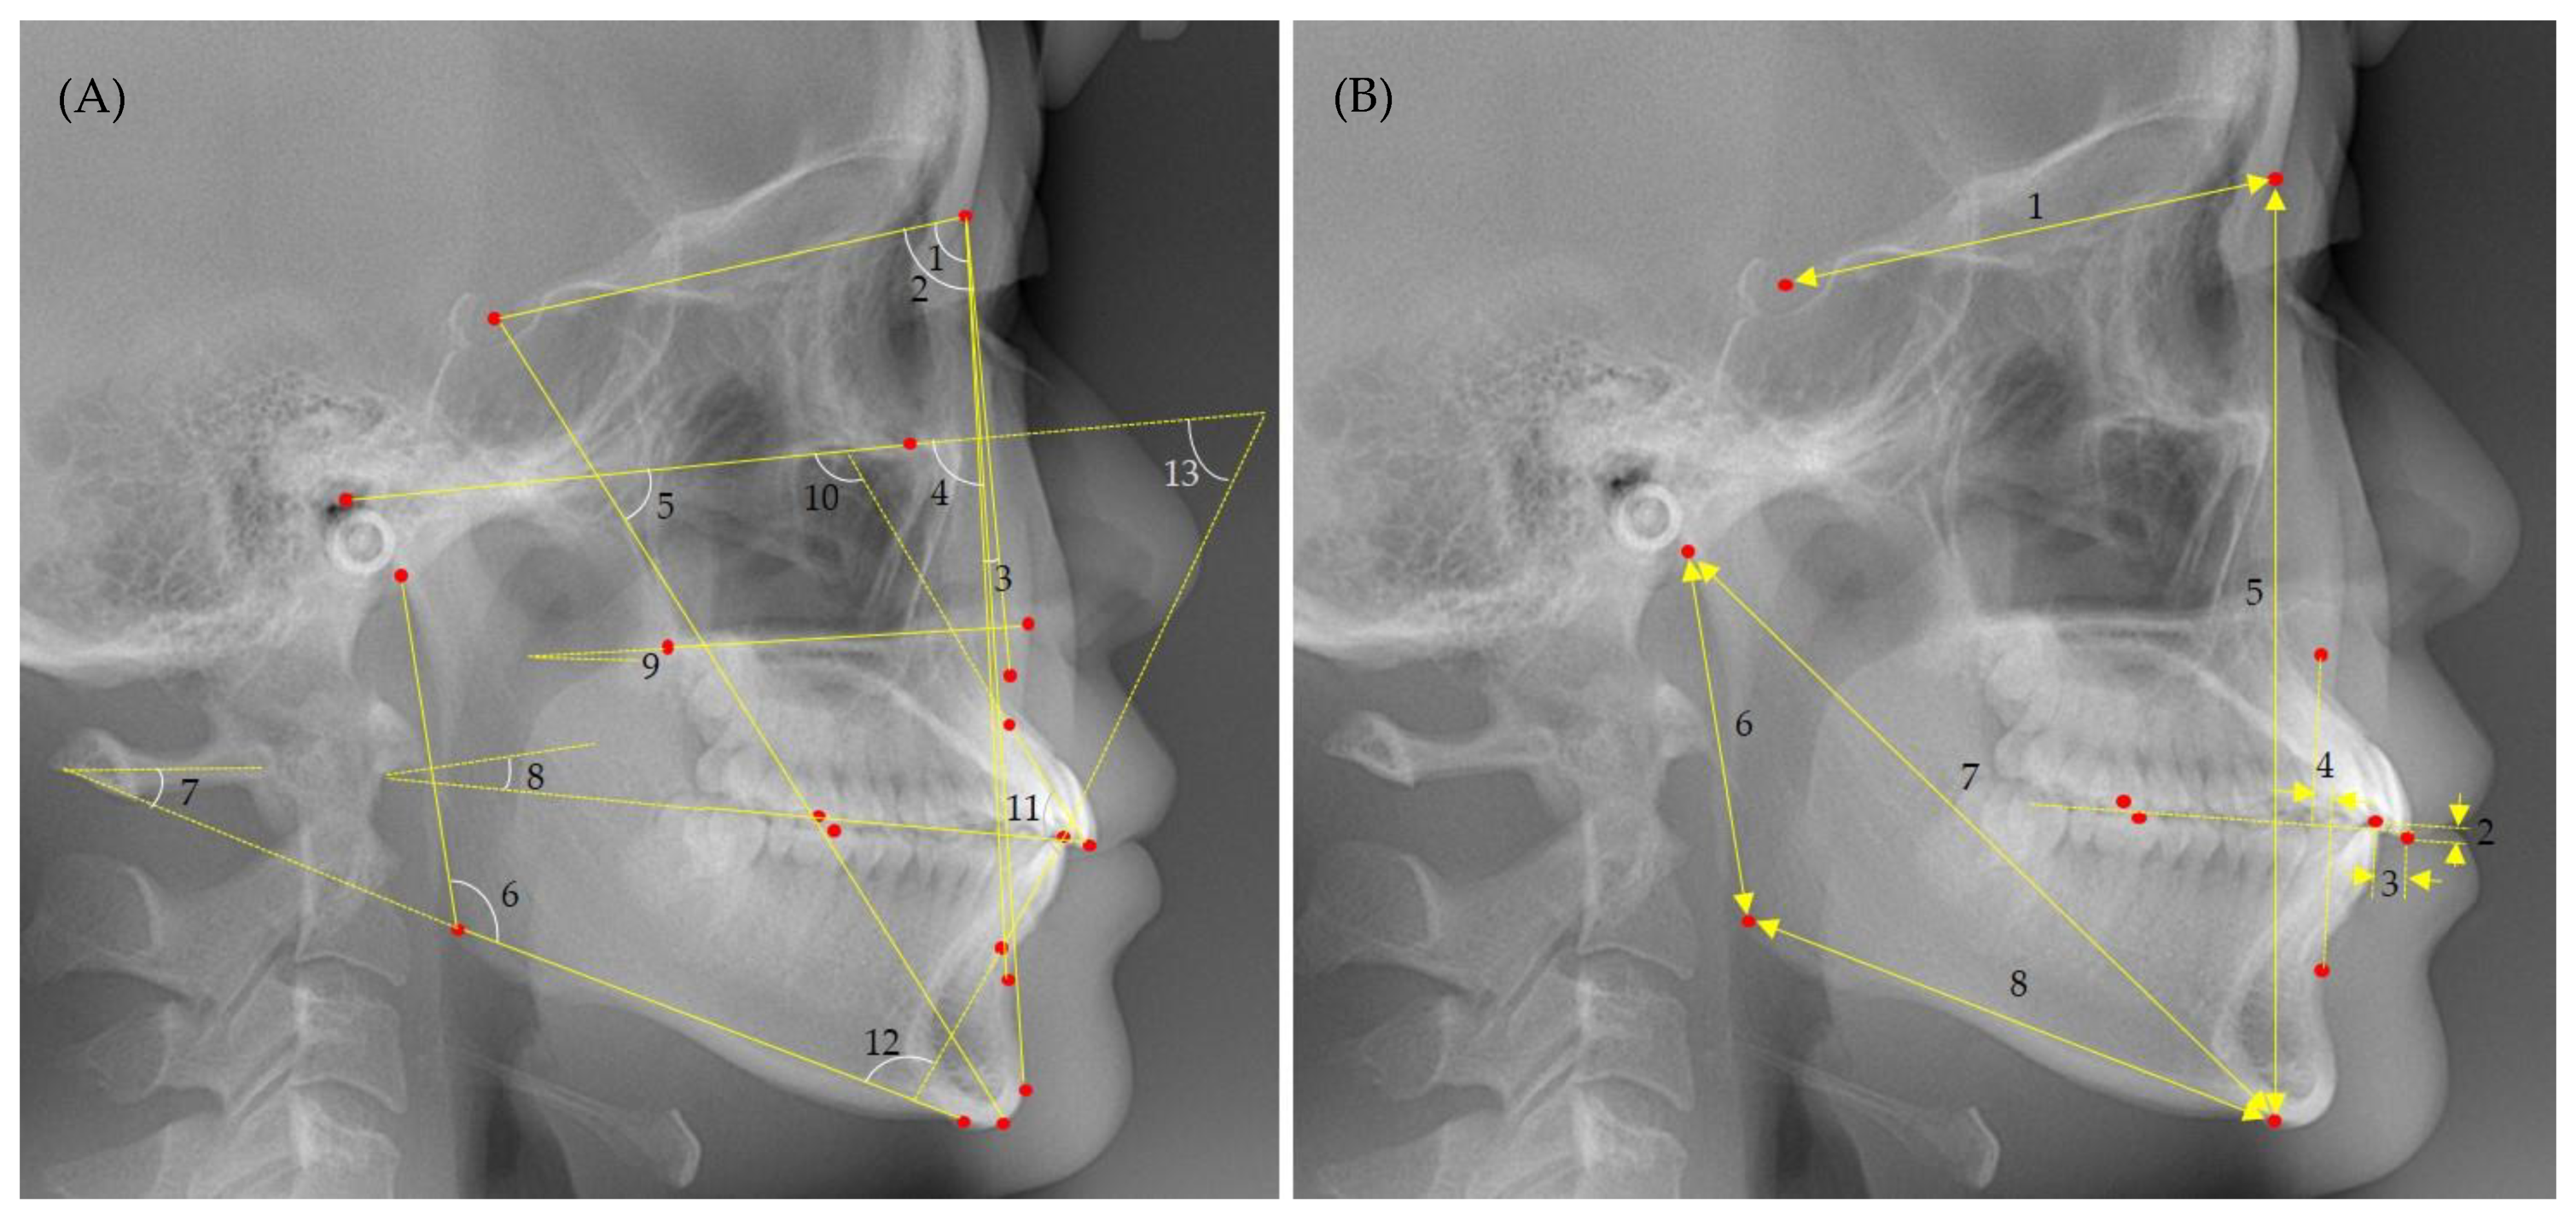

2.5.1. Craniofacial Morphology

- SNA angle: anteroposterior maxillary position relative to the anterior cranial base.

- SNB angle: anteroposterior mandibular position relative to the anterior cranial base.

- ANB angle: the anteroposterior relationship between the maxilla and mandible.

- Facial angle: chin prominence relative to the Frankfort horizontal plane.

- Y-axis: angle between the sella-gnathion line and Frankfort horizontal plane.

- Gonial angle: angle between the mandibular and ramus planes.

- FMA: divergence of the mandibular plane relative to the Frankfort horizontal plane.

- Occlusal plane angle: angle between the occlusal plane and the sella and nasion line.

- Palatal plane angle: angle between the anterior and posterior nasal spine line and Frankfort horizontal plane.

- U1 to SN: the labiolingual inclination of the maxillary central incisors relative to the anterior cranial base.

- Interincisal angle: angle between the long axes of the maxillary and mandibular central incisors.

- IMPA: labiolingual inclination of the mandibular central incisors relative to the mandibular plane.

- FMIA: labiolingual inclination of the mandibular central incisors relative to the Frankfort horizontal plane.

- SN: anteroposterior length of the anterior cranial base.

- Overbite: a vertical gap between the maxillary and mandibular central incisal edges along a line perpendicular to the occlusal plane.

- Overjet: the anteroposterior gap between the maxillary and mandibular central incisal edges along the occlusal plane.

- Wits appraisal: the anteroposterior distance between the lines extending perpendicular to the occlusal plane from points A and B.

- N-Me: the distance between the nasion and menton, indicating anterior facial height.

- Ar-Go: the distance between the articulare and gonion, indicating mandibular ramus height.

- Ar-Me: the distance between the articulare and menton, indicating effective mandibular length.

- Go-Me: the distance between the gonion and menton, indicating mandibular body length.